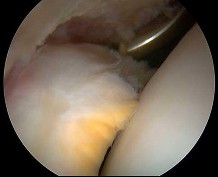

QUESTION 38

of 100

The patient undergoes hip arthroscopy and the image of the right hip is shown in Figure 39. Repair of the injured structure would be expected to improve

The radiographic studies reveal both acetabular dysplasia and cam-type femoroacetabular impingement. The MR image shows an acetabular labral tear. Structural abnormalities of the hip, including femoroacetabular impingement, have commonly been identified in association with labral tears. Disruption of the ligamentum teres is not associated with impingement conditions in the absence of trauma.

The patient has acetabular dysplasia with a decreased lateral center-edge angle and also has visible cam-type femoroacetabular impingement. The common pathway for joint degeneration in hips with cam-type femoral head anatomy includes the development of cartilage damage in the anterior or superolateral aspects of the acetabular cartilage. Paralabral cysts may be seen more commonly in association with acetabular dysplasia, although the patient’s radiographs did not demonstrate substantial cystic changes. Osteochondral loose bodies and ligamentum teres ruptures can be seen at arthroscopy in a small number of cases.

There are several proposed roles of the acetabular labrum. It can increase the depth of the acetabular socket by as much as 21% to 28%. Roles of the acetabular labrum include joint lubrication, shock absorption, and pressure distribution. Recent studies assessing the effects of loading on joint stability for both normal and dysplastic hips did not demonstrate a substantial role of the labrum in differences in loading. Although joint stability might be improved following surgical repair, acetabular dysplasia is not likely to be resolved with acetabular labral repair alone.